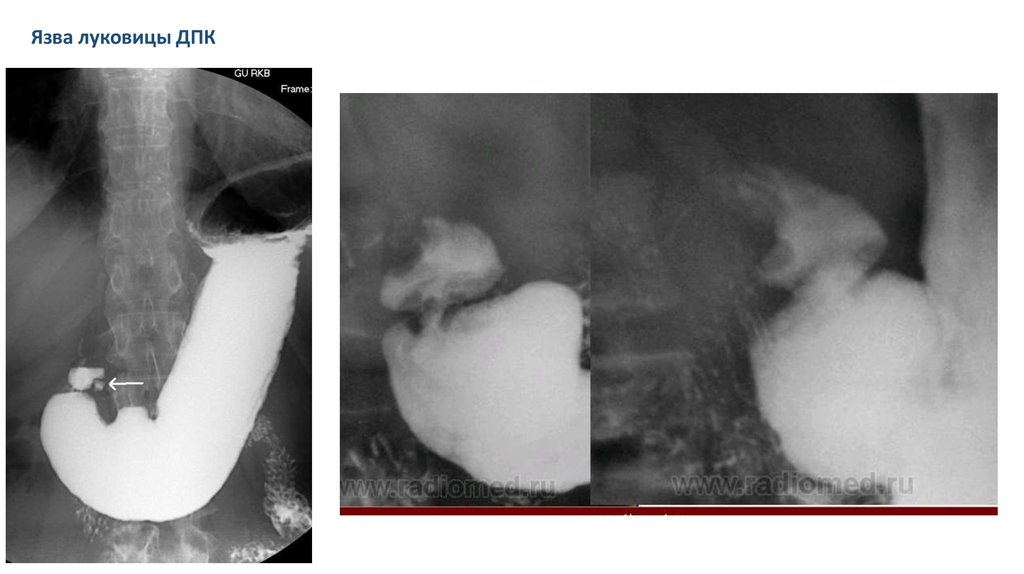

Язва луковицы ДПК

Признаки язвы желудка:

• Ниша (дефект слизистой; кратер язвы)

• Конвергенция складок

• Инфильтративный вал

вокруг стенок

• Симптом «Указывающего перста»

(локальный спазм мускулатуры; характерен для глубоких язв)